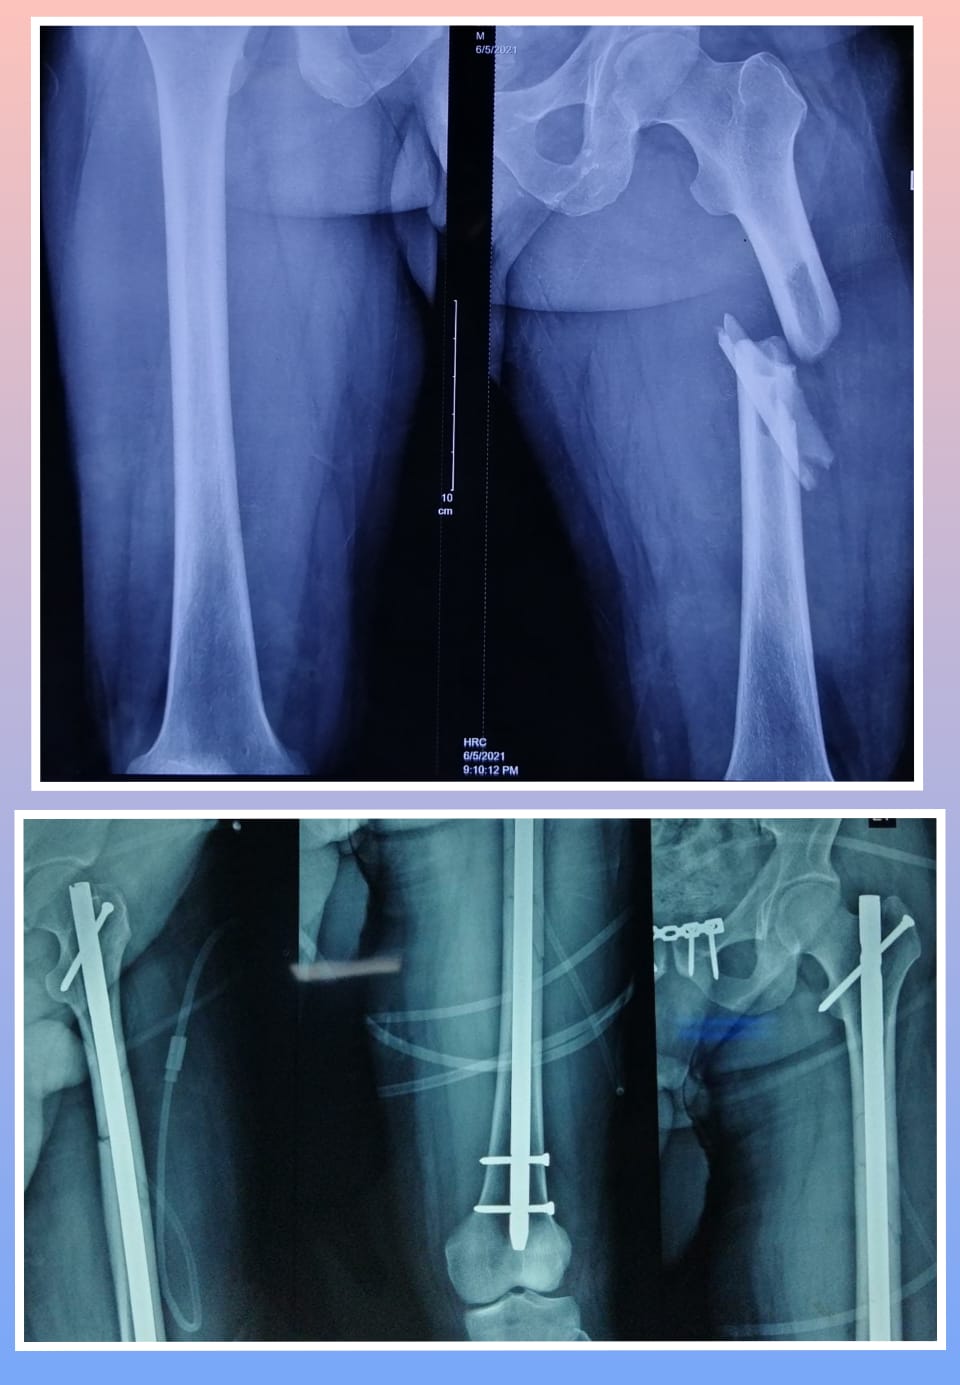

X-ray

Surgeries